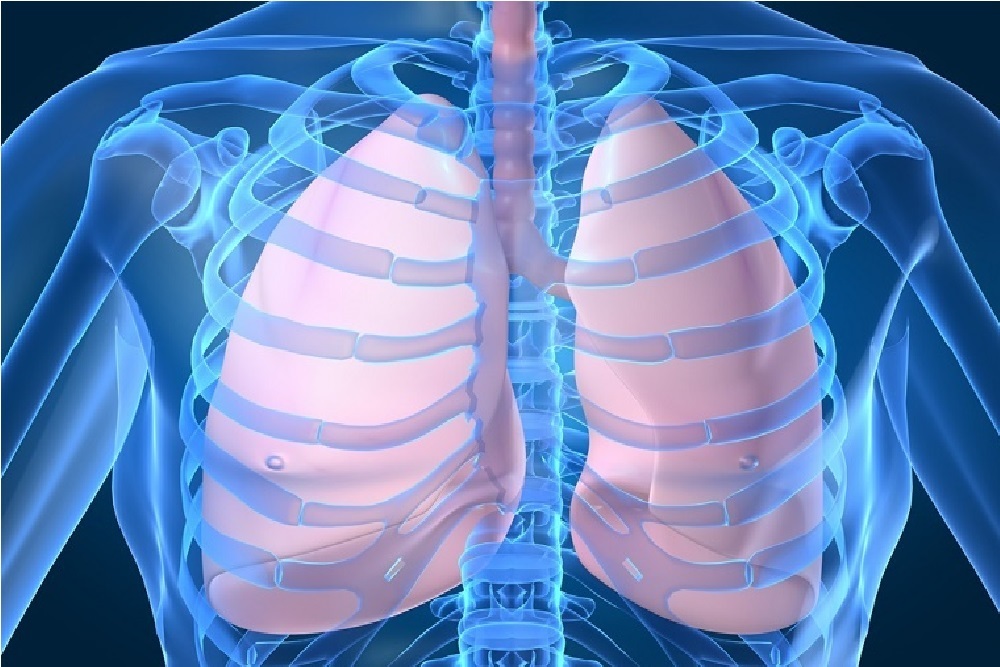

Each year we commemorate World TB Day to raise public awareness about the devastating health, social and economic consequences of tuberculosis (TB), and to step up efforts to end the global TB epidemic.

The date marks the day in 1882 when Dr. Robert Koch announced that he had discovered the bacterium that causes TB, which opened the way towards diagnosing and curing this disease.